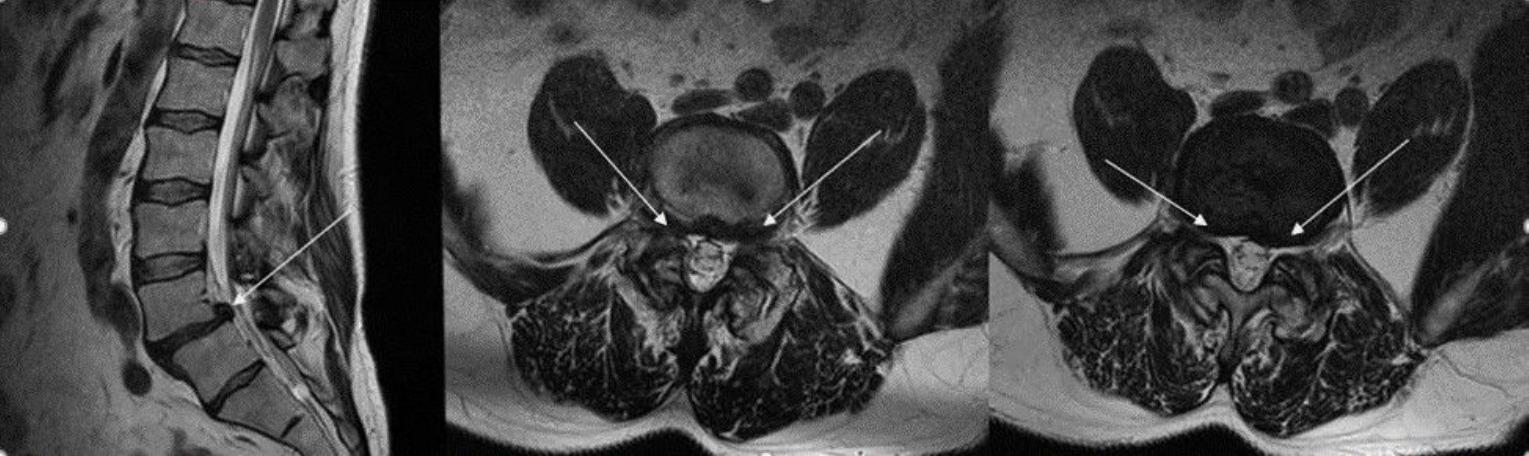

Пример МРТ. На серии МР-томограмм пояснично-крестцового отдела позвоночника, взвешенных по Т1 и Т2 в трех проекциях, выявляются признаки дегенеративно-дистрофических изменений в виде снижения высоты и интенсивности сигнала межпозвоночных дисков на Т2 ВИ с максимальной выраженностью на уровнях L4-5, L5-S1.